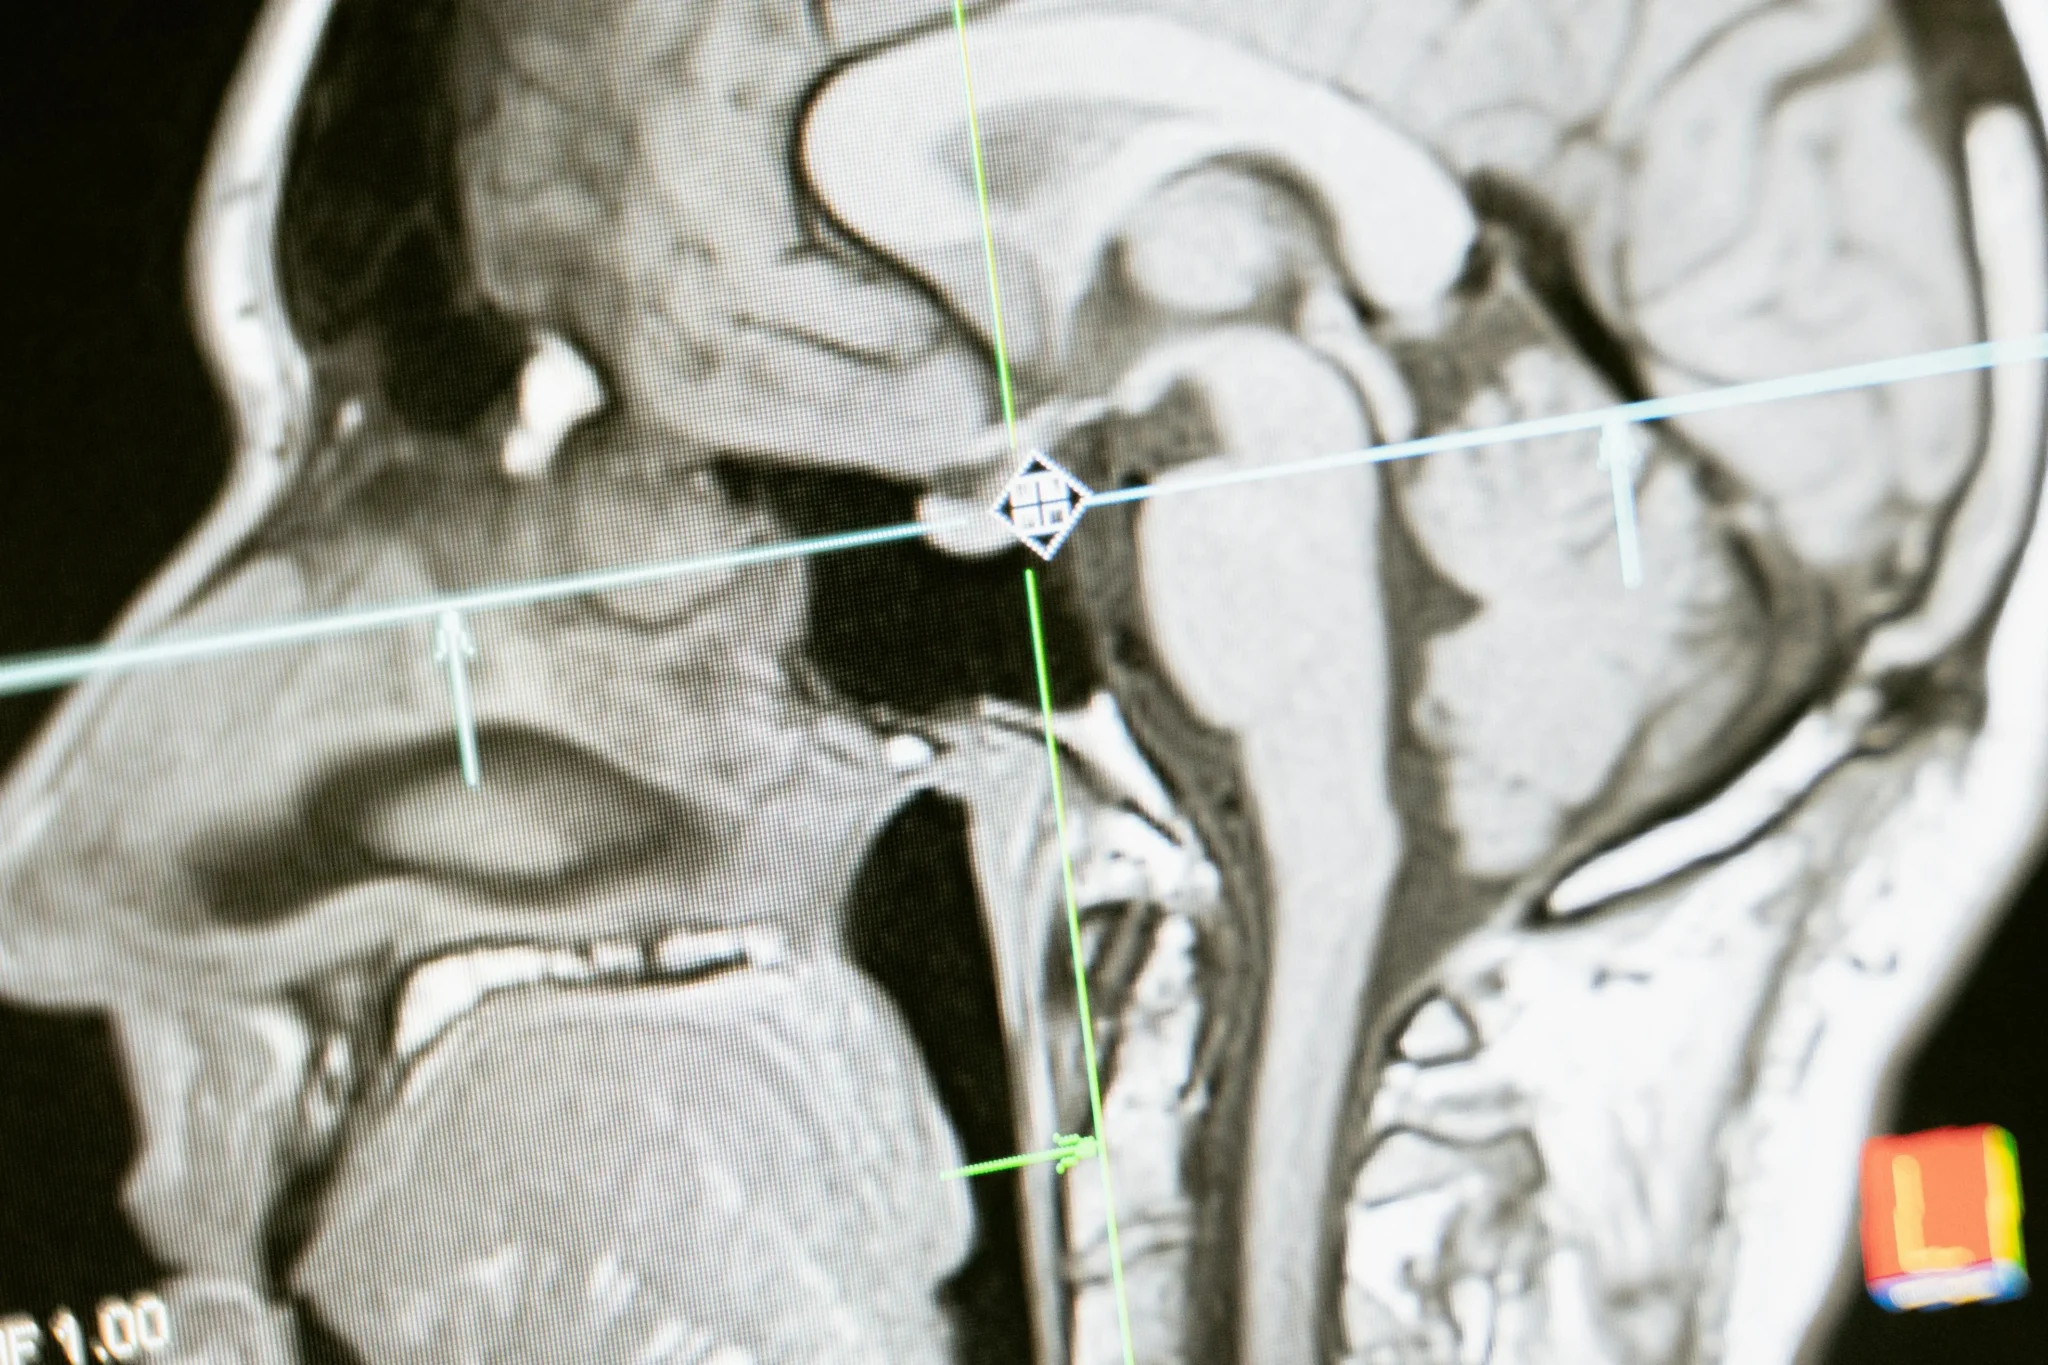

A neurocirurgia oncológica faz uso de equipamentos especiais, como a monitorização neurofisiológica intraoperatória, neuronavegação e o ultrassom intraoperatório, por exemplo, para minimizar as sequelas e garantir o sucesso da cirurgia.